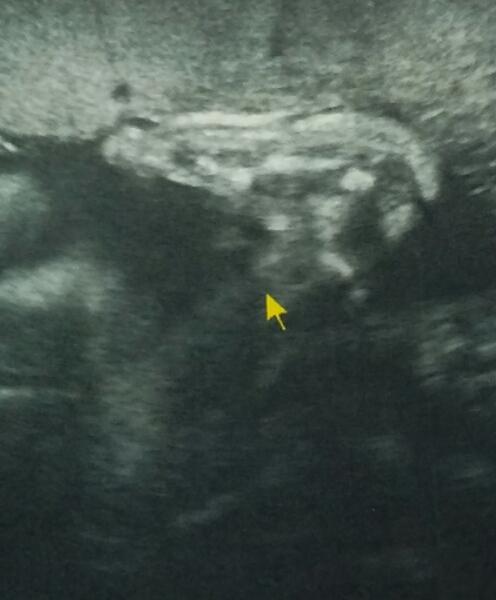

ну и я похвастаюсь😄 вчера были у Справцевой А.И. -все у нас соответствует сроку ттт, курочки мои уже 1045 и 1175😍😍 теперь понятно почему бывает так трудно дышать- просто девчонки маме делают ножками тайский массаж диафрагмы😂😂😂

@emkaemily да я даже не знаю тяжело или нет.каждый день по разному)) пока вроде нормально😊 у Справцевой мне понравилось, она все так подробненько рассказывает, но 3д мало получилось-2 маленьких кусочка, не очень четко, но видно, как чмокают))) а одна улыбнулась😍 ну двойняшек-то сложней смотреть, они прикрывают друг друга😂 папа наш сказал, что обе на него похожи😆 расскажешь потом,как сходили😉